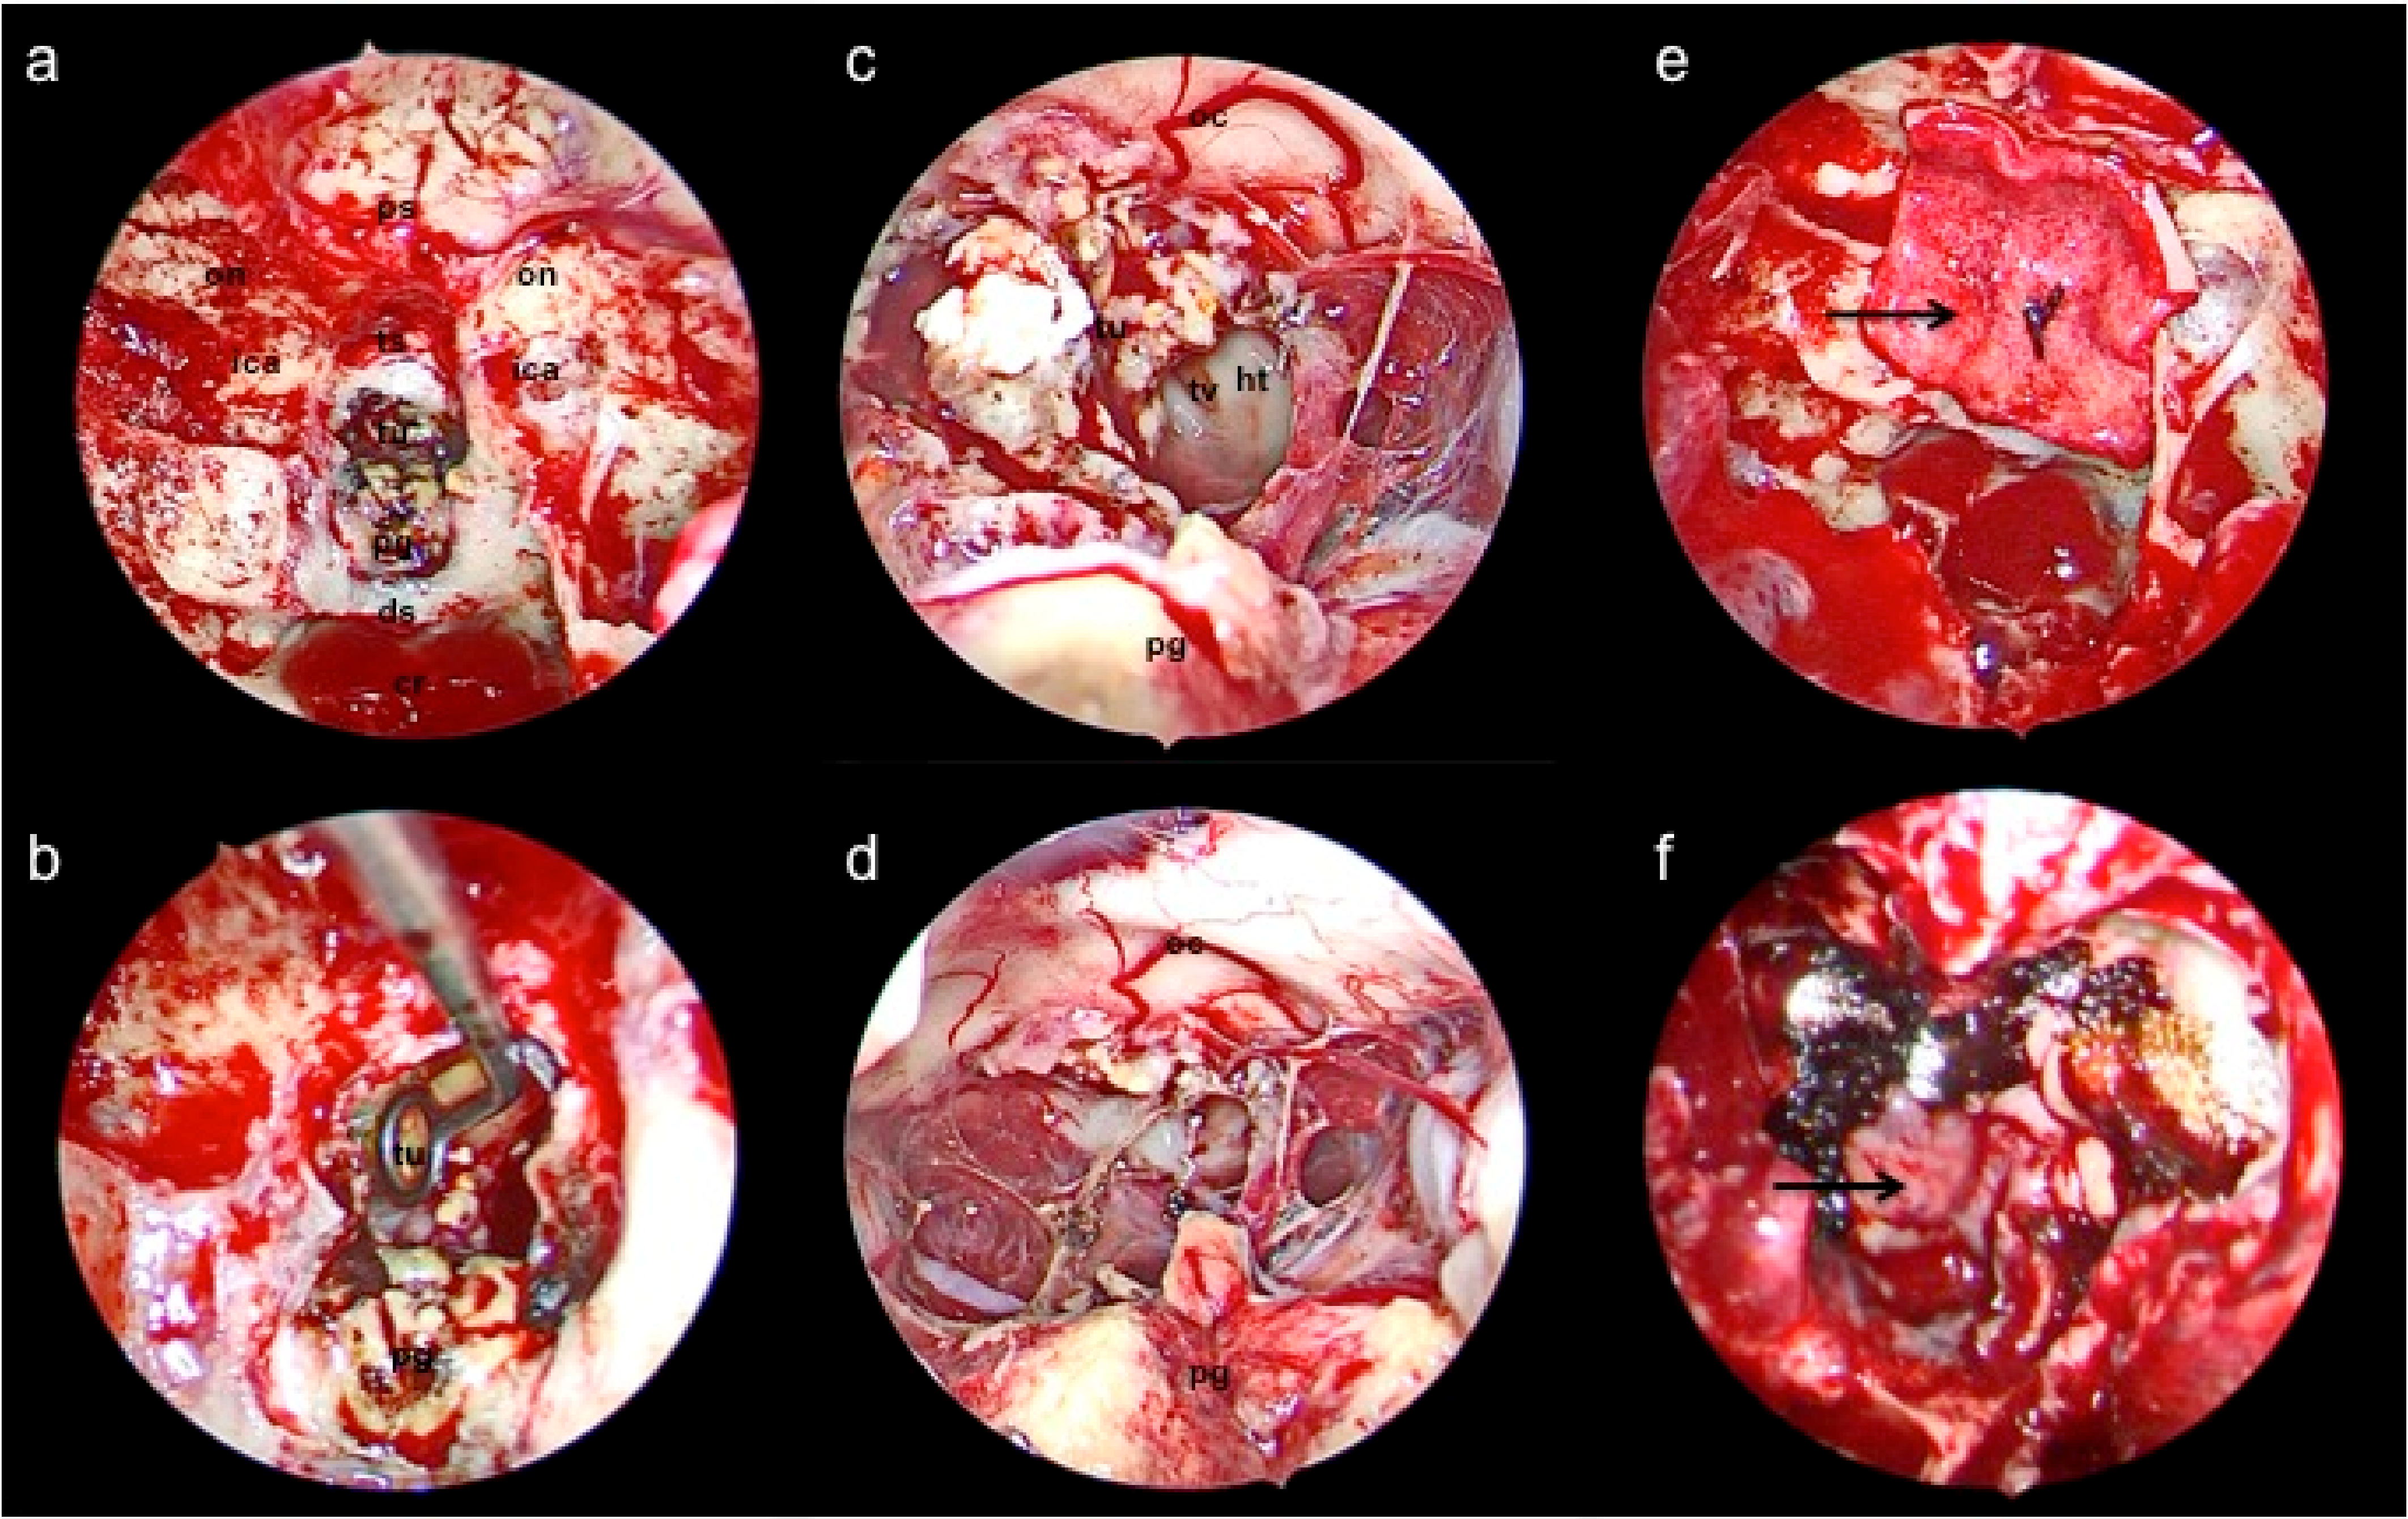

3.1. Endoscopic Endonasal Approach